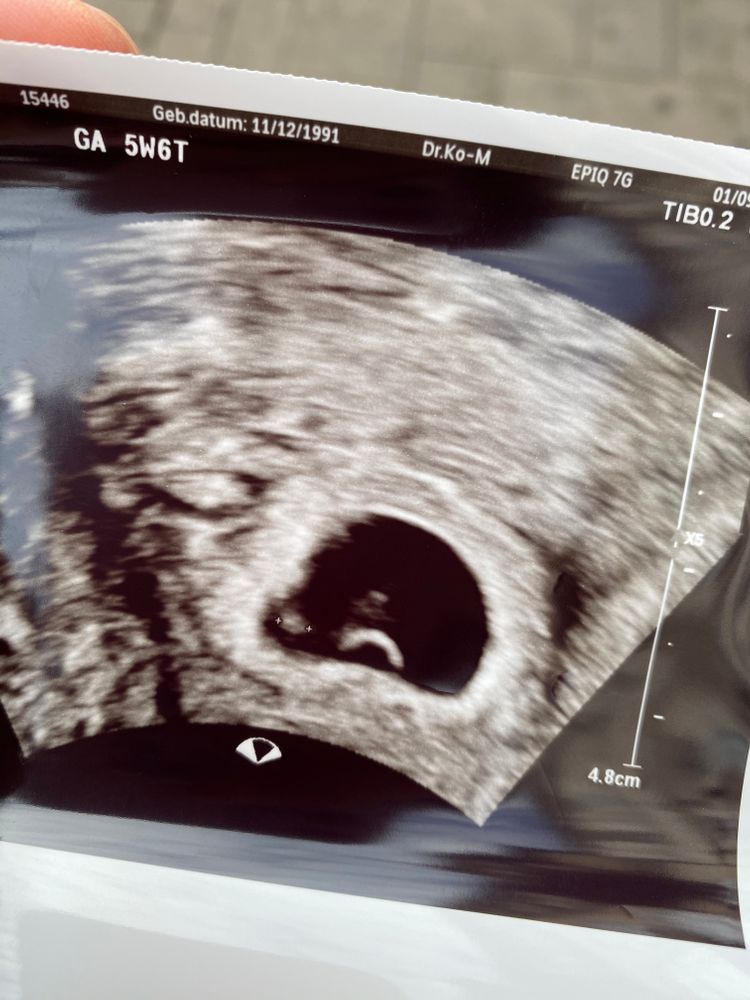

Беременность- 1 триместр ( только до 10 недель)Девочки,нас нашли,все хорошо)) Слева эмбрион 2 мм, внизу желточный мешочек,а что над ним?? Это случайно не два эмбриона?

Я что то и не спросила у врача, она быстро узи делала. Крови взяли 4 флакона, теперь через 4 недели за картой беременных. Срок день в день,5 недель 6 дней.

Чсс еще не слушали? Мне почему-то кажется, что эмбрион как раз сверху мешочка. А вот с лева не похоже на эмбрион. Хотя, вы так рано пошли, что там не разобрать. При двух эмбрионах однояйцевых должно быть тогда 2 жм